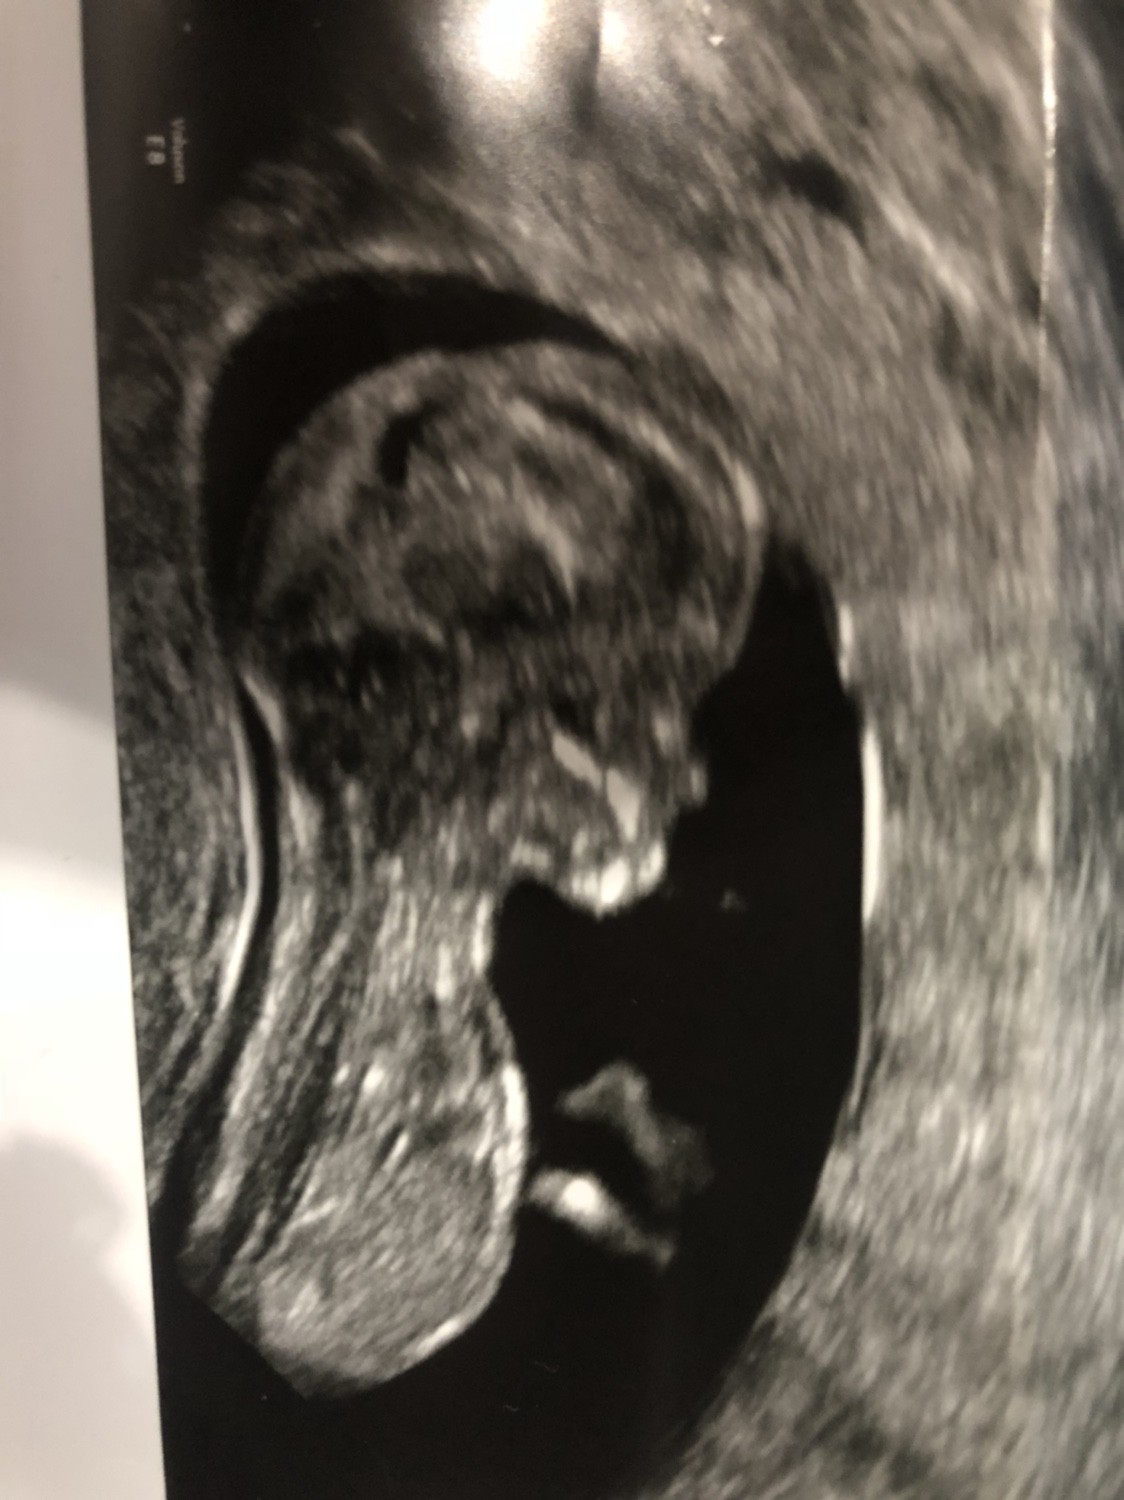

Gdzieś ktoś kiedyś pisal , że właśnie bardziej prawdopodobne jest to , ze częściej z chlopca zmienia się na dziewczynkę, chodź odwrotnie tez się zdarza, ale zdecydowanie rzadziej. Ale skąd takie info i czy jest prawdziwe to nie wiem.Dokładnieu mnie w 13 tyg córka miała być chłopcem a w 16 już ewidentna dziewczynka

teraz tez lekarz powiedział ze pewność będzie za jakod miesiąc czyli w 16 tyg